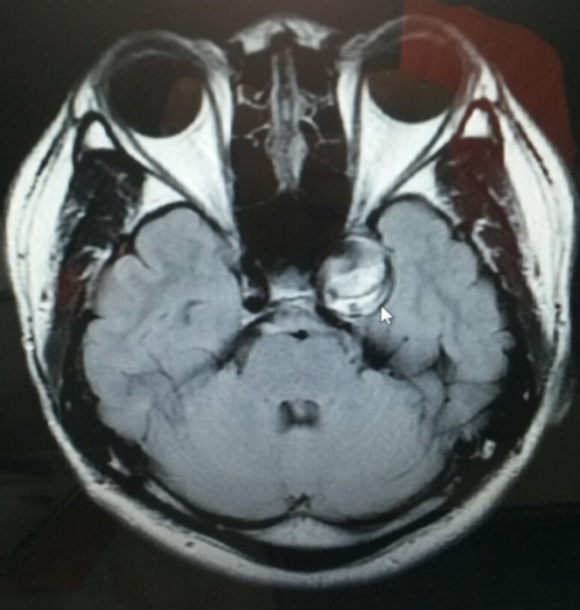

그래도 한번 가보는게 좋지 않겠냐며 마침 그주에 친한 영상의학과 전문의를 만나러 간다고 하셔서 검사도 받을 겸 따라가서 찍었던 MRI 판독지는

의학적 지식이 하나도 없는 내가 봐도 뭔가 문제가 있어 보였다.

이후 혈관조영술이라는 더 내혈관을 자세히 볼수 있는 시술을 마친후에 내 머릿속에 "거대 뇌동맥류" 라는것이 있는걸 확인할수 있었다.